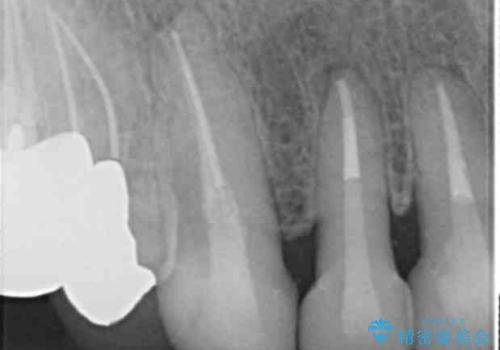

- 前歯のセラミック治療から4年半経過した患者様です。

4年ぶりに来院して下さいました。

治療した上の前歯6本は全く問題なく、「獅子舞みたいだった前歯を綺麗にして下さってありがとうございました!」と再度お礼を言って下さいました。

4年半前のクラウン装着時と変わらず、まるで天然歯のように自然に見えました。

患者様の良好なセルフケアと精密な適合の良いクラウンにより、歯肉の腫脹や退縮も認められませんでした。

4年半前に行った治療に大変ご満足頂き、他の部位の治療のため再来院して下さいました。